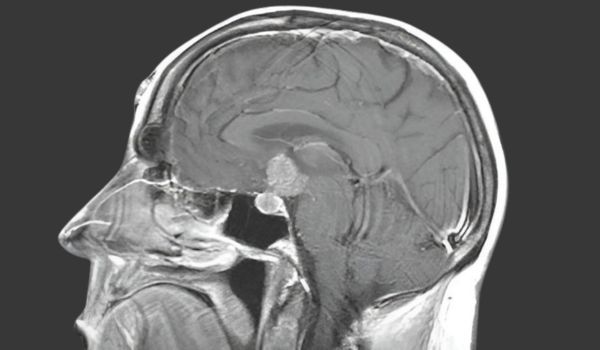

МРТ-діагностика гіпофіза та патології орбіт